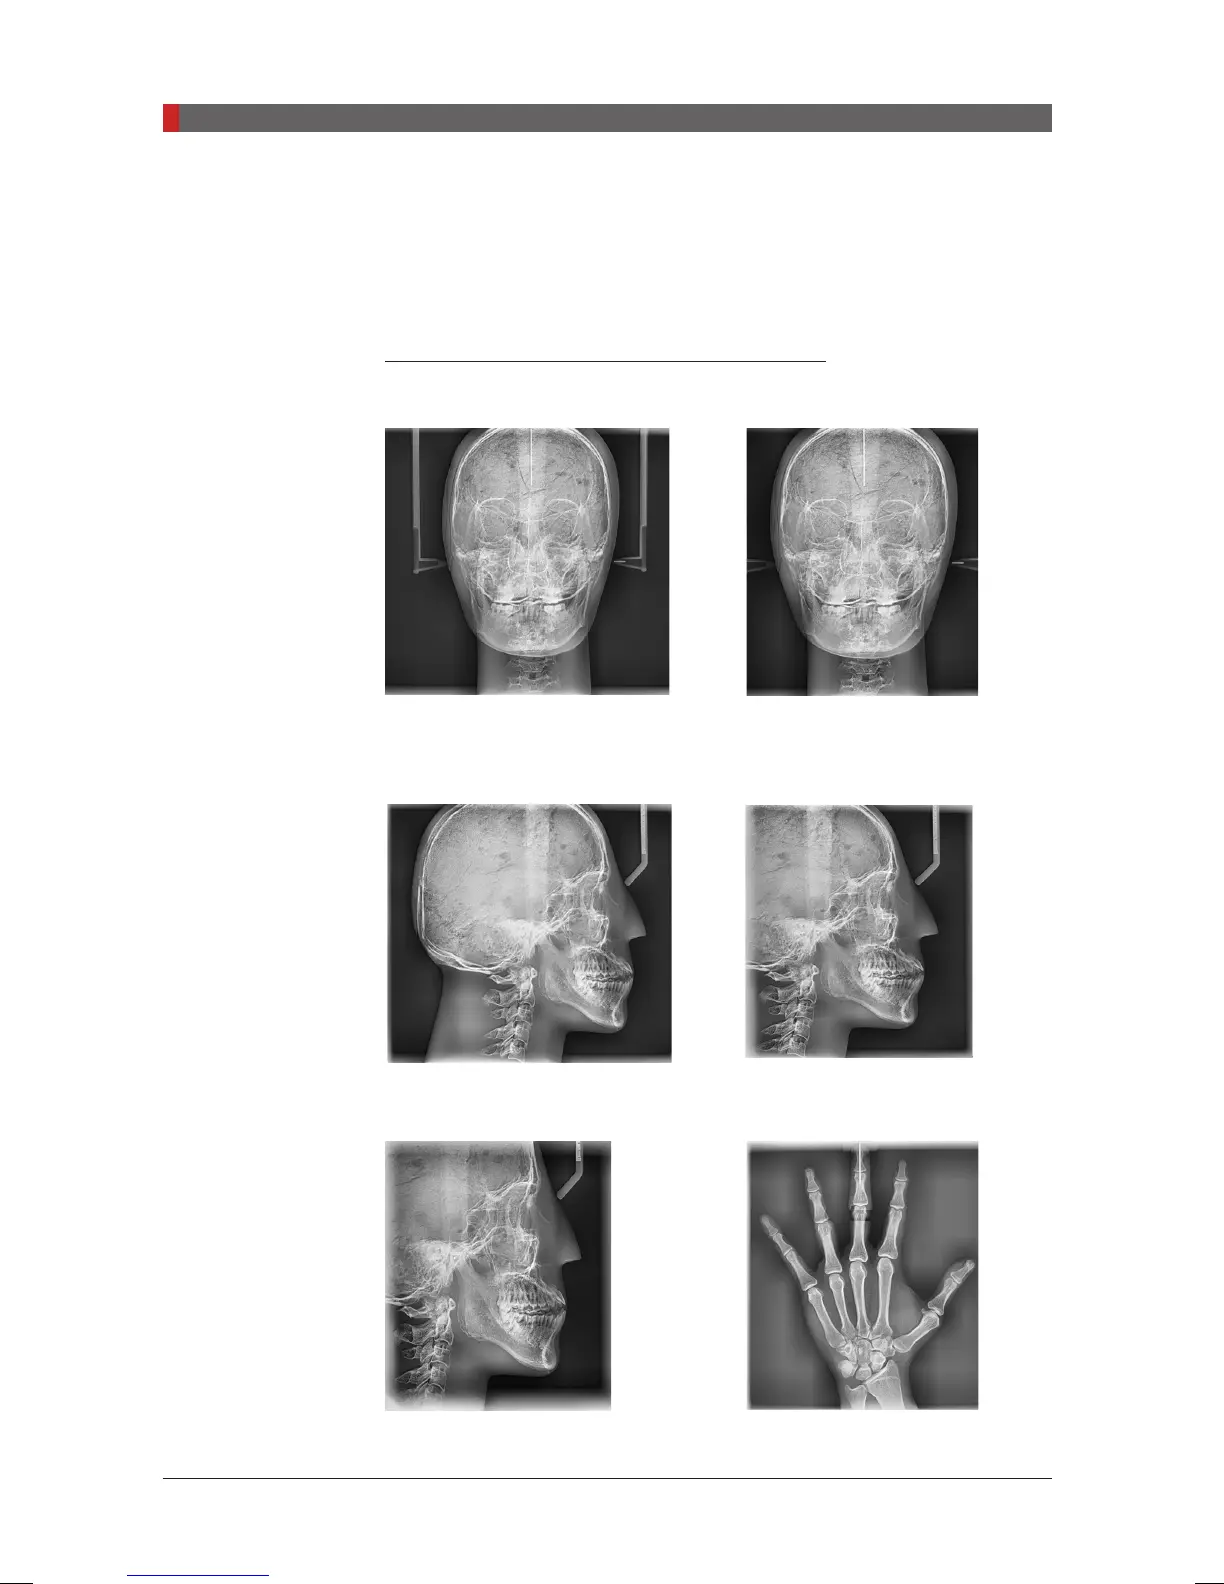

Sample images: with one shot type sensor

PA: Posterior – Anterior

FOV 12 x 10

(inches)

30.48x25.40

(cm)

FOV 9 x 10

22.86x25.40

Lateral

Full Lateral : FOV 12 x 10

Lateral : FOV 9 x 10

FOV 8 x 8

20.32x20.32

Carpus